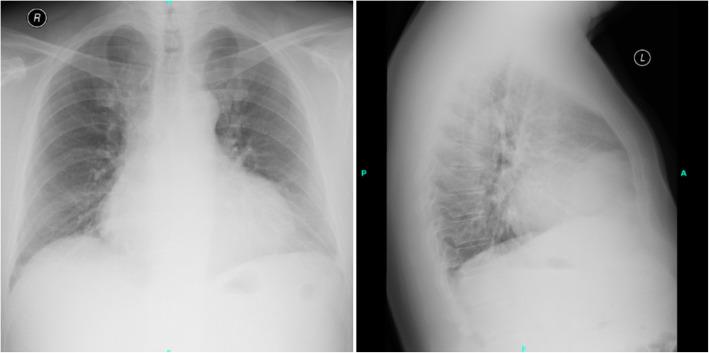

Forty-eight-year-old diffuse large B cell lymphoma patient was admitted to our emergency department with chest pain, effort dyspnea, and fever. The patient had normal blood pressure, blood oxygen saturation, sinus tachycardia, fever, crackles over the left lower lobe, novum incomplete right bundle branch block with Q waves and minor ST alterations, elevated C-reactive protein, high-sensitivity troponin-T, and d-dimer levels. Chest X-ray revealed consolidation on the left side and enlarged heart. Bed side transthoracic echocardiography showed inferior akinesis with pericardial fluid. Coronary angiography showed no occlusion or significant stenosis. Chest computed tomography demonstrated the progression of his lymphoma in the myocardium. He was admitted to the Department of Hematology for immediate chemotherapy and he reached complete metabolic remission, followed by allogeneic hematopoietic stem cell transplantation. Unfortunately, about 9 months later, he developed bone marrow deficiency consequently severe sepsis, septic shock, and multiple organ failure what he did not survive.

一名48岁的弥漫性大B细胞淋巴瘤患者因胸痛、劳力性呼吸困难和发热入住我院急诊科。患者血压正常、血氧饱和度正常、窦性心动过速、发热、左下叶可闻及湿啰音、新出现的不完全性右束支传导阻滞伴Q波和轻微ST段改变、C反应蛋白升高、高敏肌钙蛋白T及D - 二聚体水平升高。胸部X线显示左侧实变及心脏增大。床旁经胸超声心动图显示下壁运动减弱伴心包积液。冠状动脉造影显示无闭塞或明显狭窄。胸部计算机断层扫描显示其淋巴瘤在心肌内进展。他被收入血液科立即进行化疗,并达到完全代谢缓解,随后接受异基因造血干细胞移植。不幸的是,约9个月后,他出现骨髓抑制,继而发生严重脓毒症、感染性休克和多器官功能衰竭,最终死亡。